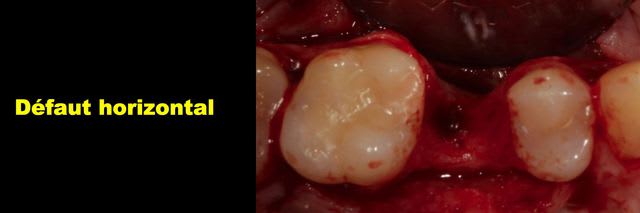

Bon j'ai extrait la dent et maintenant y a un gros trou.

Img 3472 m6qobf - Eugenol

Img 3473 xs5juw - Eugenol